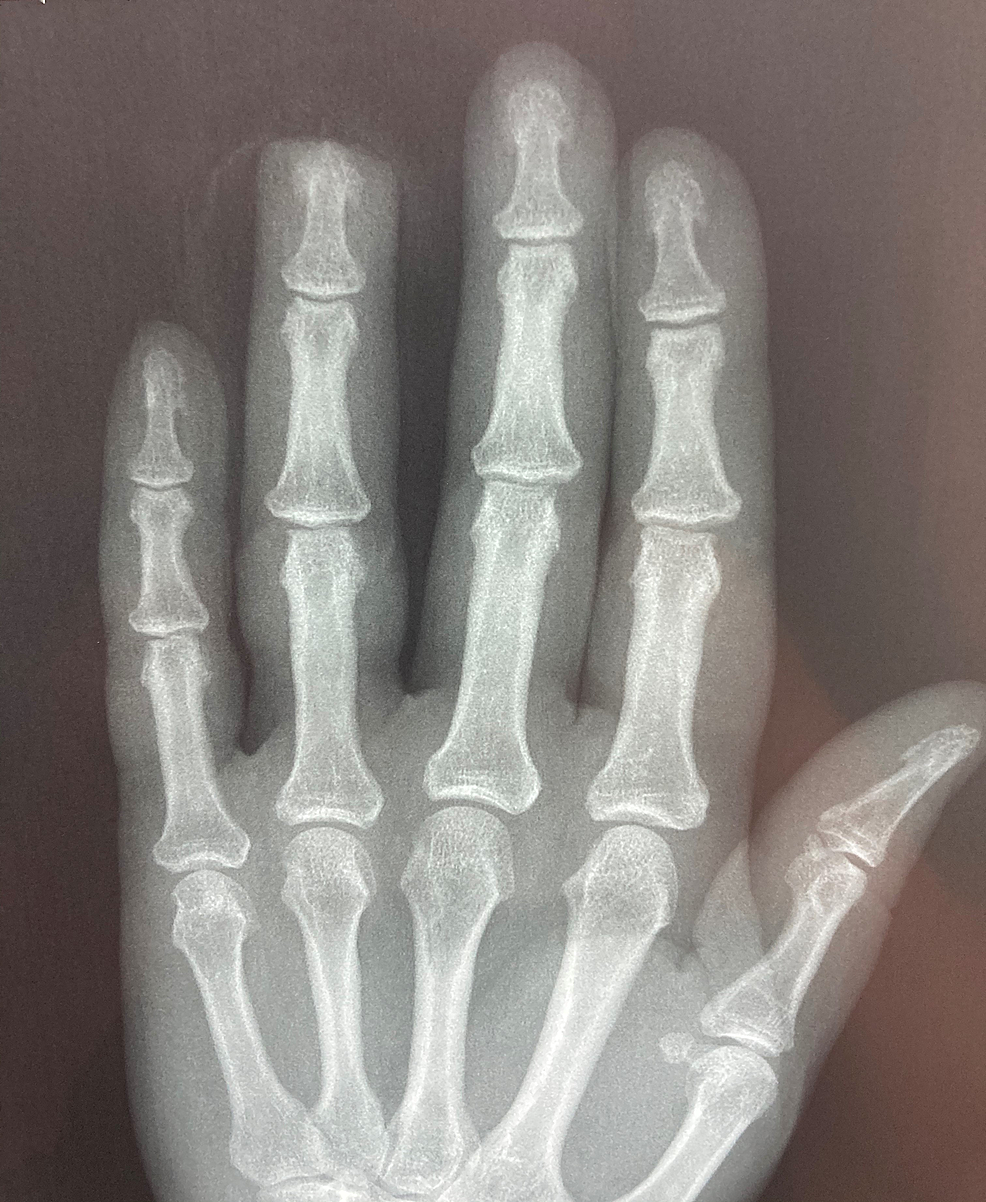

Allen stage III reconstruction before surgery (upper) and at 13 months Finger Tip Injury Allen the fingertip can be injured by a number of forces but lacerations are most frequent, followed by deforming crush. this activity reviews the cause and presentation of fingertip injuries and highlights the. two simple systems are the allen 6 and fassler 7 classification schemes. we report our new fingertip injuries outcome score (fios) based on finger. Finger Tip Injury Allen.